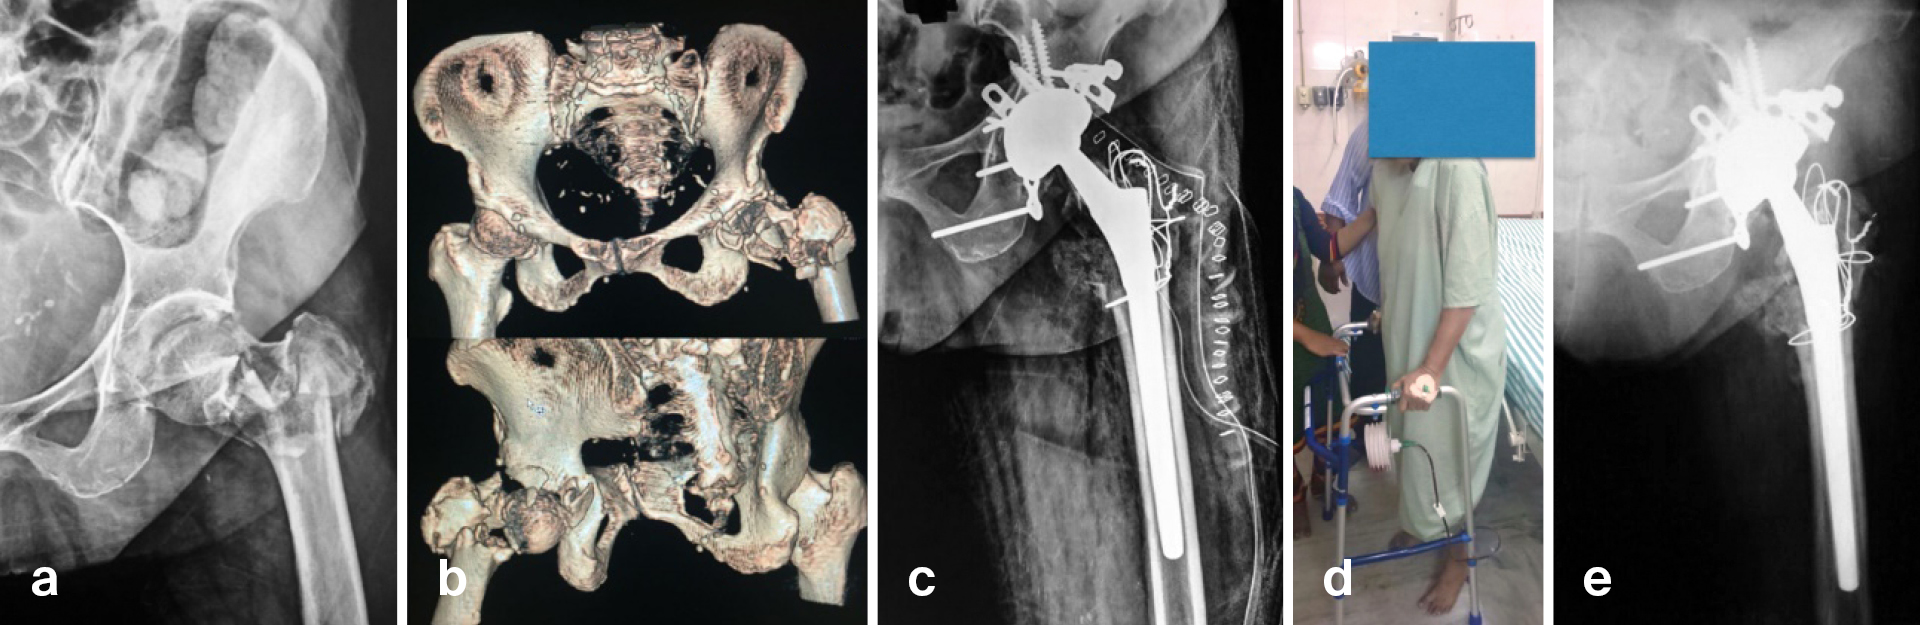

With anatomical reduction being possible only in about 50% of geriatric acetabular fractures [6], it is very important to consider THA with supplemental ORIF in a wide variety of injury patterns. Apart from poor acetabular injury characteristics, such as chondral impaction, comminution, and associated fractures in the femoral neck or head (Figure 1), important patient characteristics like osteoporosis, age, gender, and associated medical comorbidities should also be considered when choosing THA with ORIF or ORIF alone. Given that some of the more recent literature has reported a higher incidence of medical and surgical complications with acute THA and supplemental ORIF [7, 8], it is important to carefully weigh risks against benefits of this technically complex procedure. If THA can be performed through the same surgical approach used for ORIF, or by extending it, then it is less likely to be riskier than ORIF alone. ORIF of both columns through separate surgical approaches combined with THA in a single setting can be associated with increased morbidity but, if needed, can be staged to minimize risks.